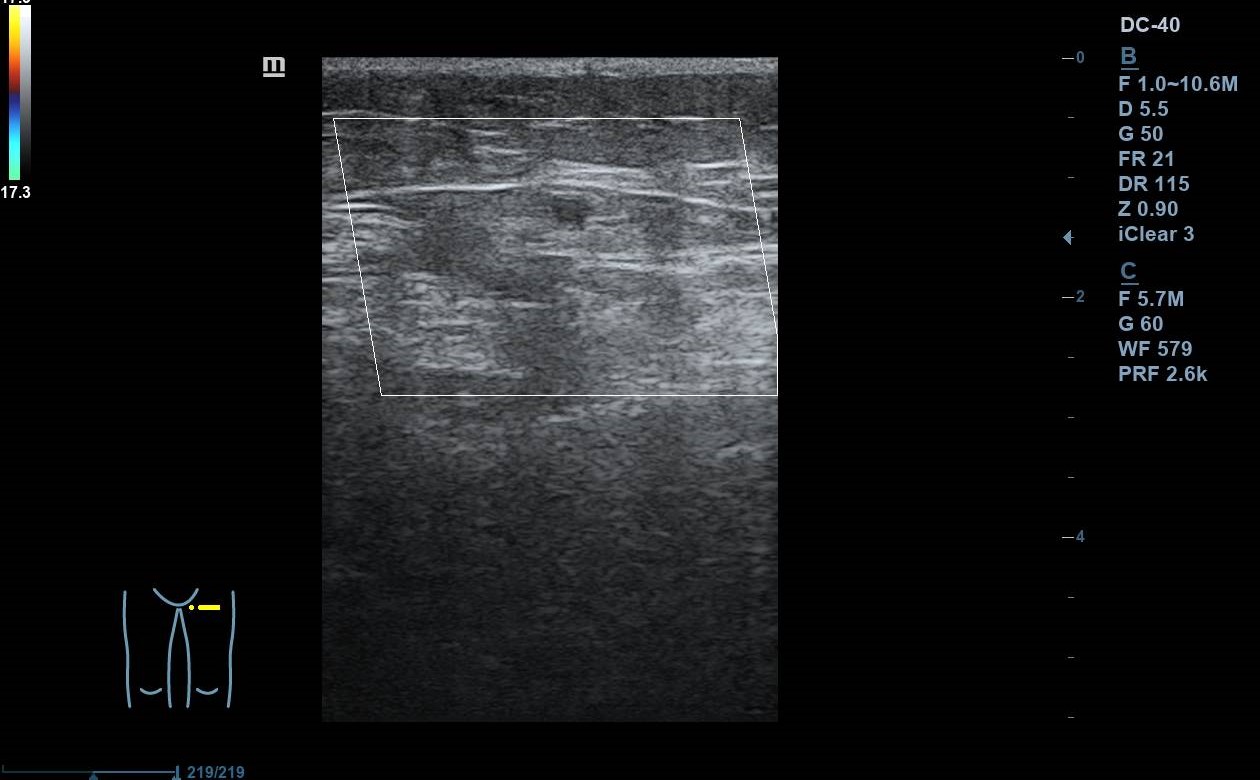

Se realiza ecografía Doppler en el Centro de Salud: se exploran con sonda lineal ambos MMII a nivel inguinal y poplíteo, constatando colapsabilidad, presencia de flujo y ausencia de material ecogénico a nivel de vena femoral común y poplítea. Colocando sonda en el punto doloroso observamos vena safena interna no colapsable. Nos desplazamos superiormente, siguiéndola hasta la unión safenofemoral, sin observar colapsabilidad durante el trayecto.

Juicio clínico: TVS en vena safena interna de al menos 5 cm con afectación próxima a cayado.

Un mes después se repite ecografía en el centro de salud observándose mejoría de la TVS.